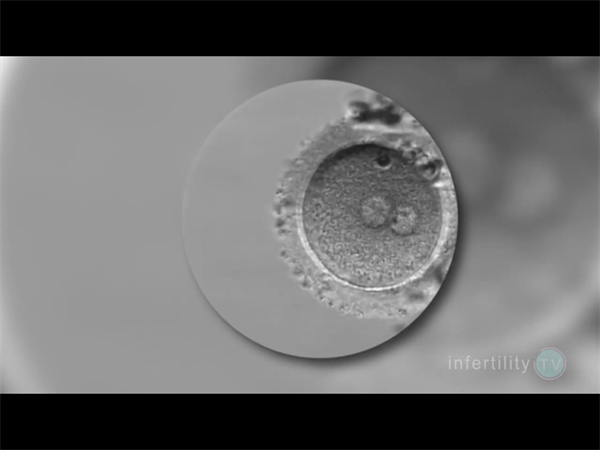

在借助第三方卵子完成试管周期后,前三个月是胚胎扎根与发育的关键阶段。部分准妈妈可能面临HCG翻倍不理想、孕酮水平持续偏低的情况,这需及时通过科学干预稳定妊娠。以下从认知到行动,梳理全面的保胎思路。

HCG由胚胎滋养层细胞分泌,其水平随孕周增长快速上升,是反映胚胎活性的重要指标;孕酮由卵巢黄体及后续胎盘分泌,能维持子宫内膜容受性,支持胚胎发育。两者协同保障早期妊娠稳定。